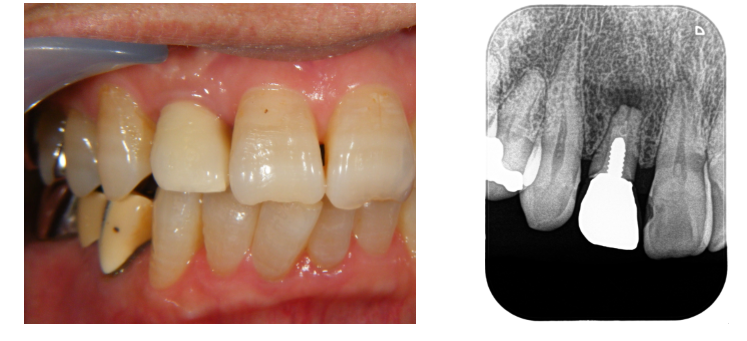

右上前から2番目の歯根の先端に膿がたまり、腫れと痛みがあるケースでした。

歯根の状態が悪く、保存するのは厳しいと判断しました。

抜歯する前に、CTで骨の状態を詳しく診査し、抜歯と同時にインプラントを行うことにしました。

抜歯即時で治療したことにより、歯肉の形態を保存することが出来ました。